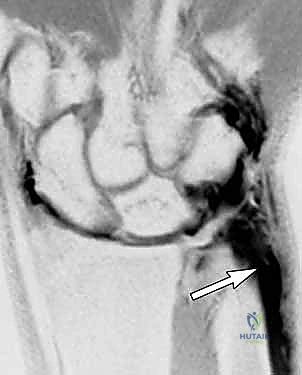

FIG 3 • B. The coronal MRI arthrogram projection illustrates leakage of the opaque dye into the ECU fibro-osseous subsheath.

An MRI arthrogram can be particularly useful, depicting a subsheath tear and, by extension, an injury to the peripheral TFCC, with contrast extravasating into the sixth extensor compartment. This study also provides invaluable information on the remainder of the TFCC and the integrity of intercarpal ligaments.